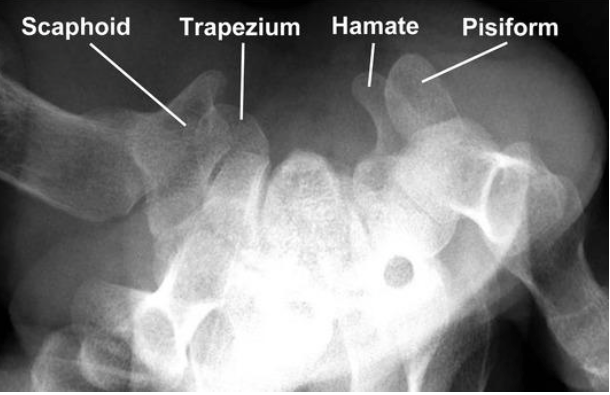

What is the epidemiology of scaphoid fractures?

- Most frequently fractured carpal bone

- Accounts for up to 15% acute wrist injuries

- location

- waist -65%

- Proximal third- 25%

- Distal third 10%

- distal pole is most common location in kids due to ossification sequence

Describe the anatomy of the scaphoid?

- 75% scaphoid covered in CARTILAGE

- Blood supply

- major supply- DORSAL CARPAL Branch of radial artery- enters scaphoid in a nonarticular ridge on dorsal surface and supplies proximal 80% scaphoid via a RETROGRADE blood flow

- minor via SUPERFICIAL PALMAR Arch branch of volar radial artery- enters DIstal TUBERCLE and supplies 20% DISTAL SCAPHOID

What investigations are useful in DDx scaphoid fracture?

- Xrays

- AP and lateral

- Scaphoid view- 30o wrist extension, 20o ulnar deviation

- 45o pronation view